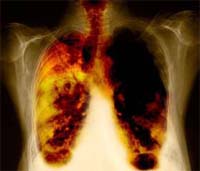

Ung thư phổi là loại ung thư gây chết người phổ biến nhất trên thế giới. Tại Anh, mỗi ngày có khoảng 100 người được chẩn đoán mắc bệnh ung thư, và cứ 5 người thì có một người bị tế bào ung thư phổi nhỏ. Tỷ lệ sống sót của người bệnh ung thư phổi loại này rất thấp: chỉ ba phần trăm trong số các bệnh nhân có thể sống thêm được 5 năm sau khi điều trị.

Trong thể Ung thư phổi tế bào nhỏ, các khối u lan tỏa rất nhanh nên rất ít có khả năng loại bỏ chúng bằng phẫu thuật. Mặc dù ngay lần đầu tiên có sự đáp ứng trong biện pháp hóa trị và có hay không kết hợp với xạ trị, các khối u vẫn sớm quay trở lại và phát triển khá nhanh chóng.